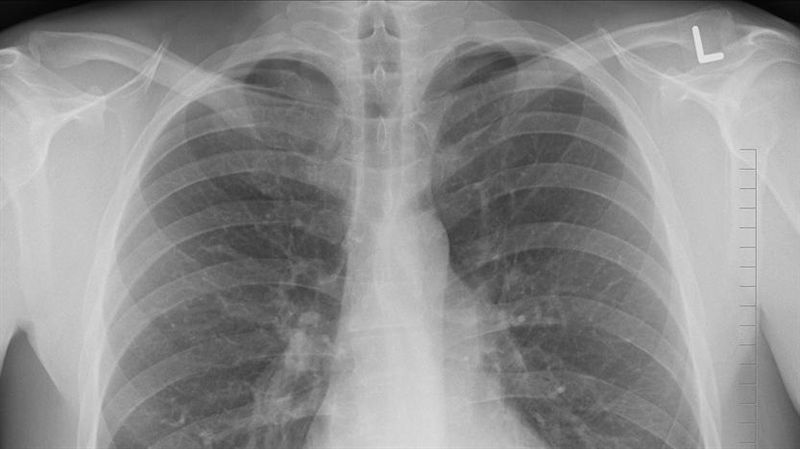

醫師表示.肺結核是由結核菌所引起的傳染病,因症狀不典型,容易讓病人本身及醫師延誤了診斷。(示意圖/資料照)

在檢查與治療上,肺結核的診斷,最重要的依據是胸腔X光檢查。臨床症狀考慮到肺結核時,可以以胸腔X光做最快速的篩檢,若有疑似病灶,進一步的痰液檢查,包括痰液抗酸俊染色抹片檢查及痰液結核菌培養可確診肺結核。結核病是個可治癒的疾病,治療以口服藥物為主。規則服藥兩週以上,體內結核菌量會減低99%以上,大大減低了傳染的可能性。